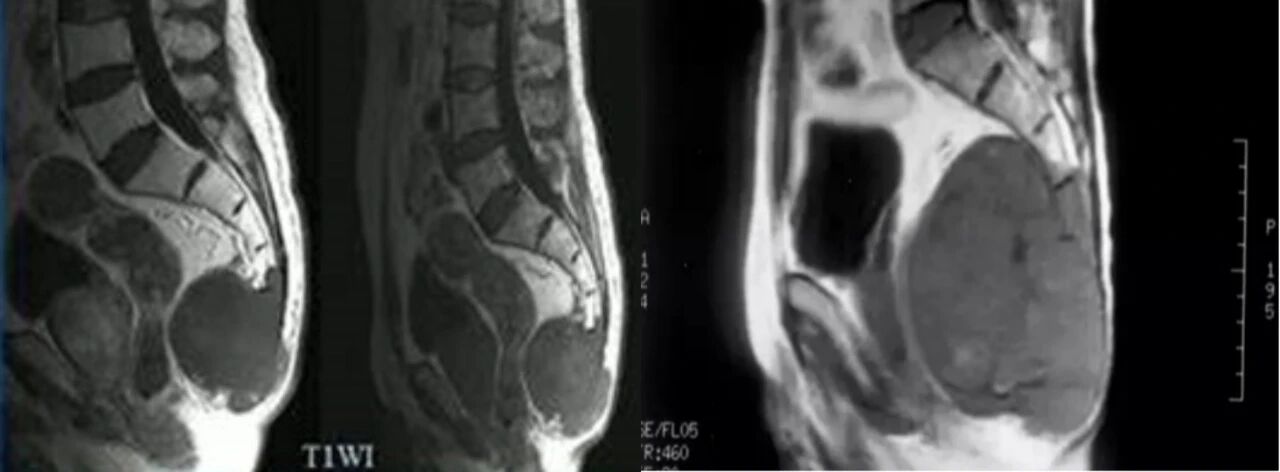

一、患者男,52岁,骶尾部脊索瘤术后复发,2021年5月17日行重离子治疗。

治疗前2021年5月12日 治疗后2022年7月28日